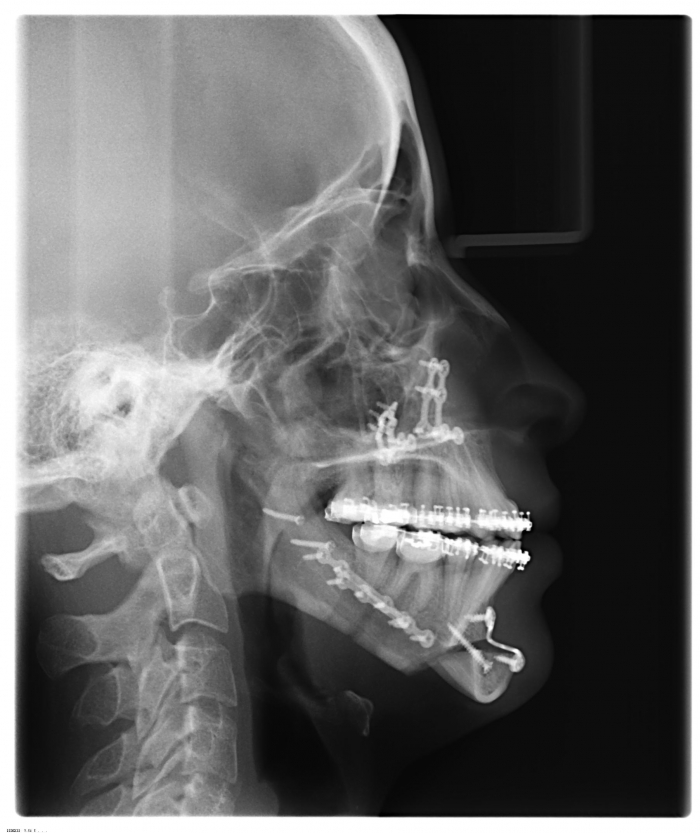

Raio x inicial

Raio x após a cirurgia realizada em 2015